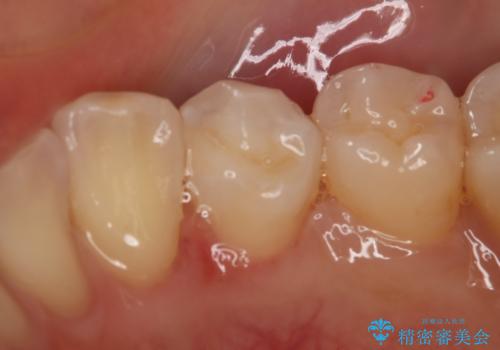

- 右下4番の虫歯治療を希望され来院された患者様です。

セラミックでの治療を希望されたため、切削量・形態を考慮しセラミックインレーでの治療を計画しました。

う蝕を除去した後、CRで裏層した上で形成、印象をしています。

装着時にはラバーダムを使用しています。